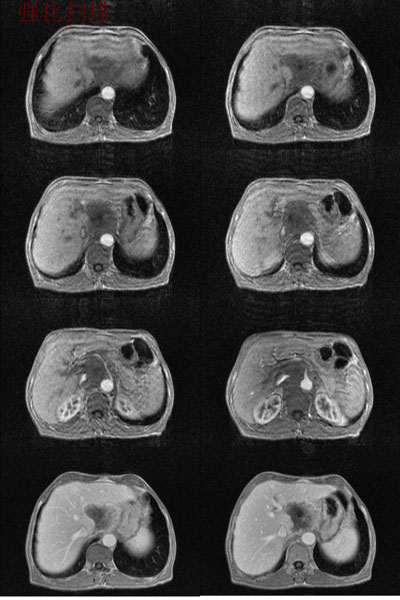

男:62岁:右上腹痛1月。b超报告肝左叶外侧段占位。请讨论灶来源!谢谢!!

腹主动脉前肝左叶后方占位,局部与肝脂肪间隙尚存,故排除左肝来源病变.病灶主体层面位置较高,胰腺受压前移.腹腔干明显拉长包埋.增强后肿瘤边缘性强化.胃小弯侧血管明显增粗.

考虑;后腹膜来源肿瘤.神经源性肿瘤>间叶源性肿瘤>淋巴源性肿瘤.